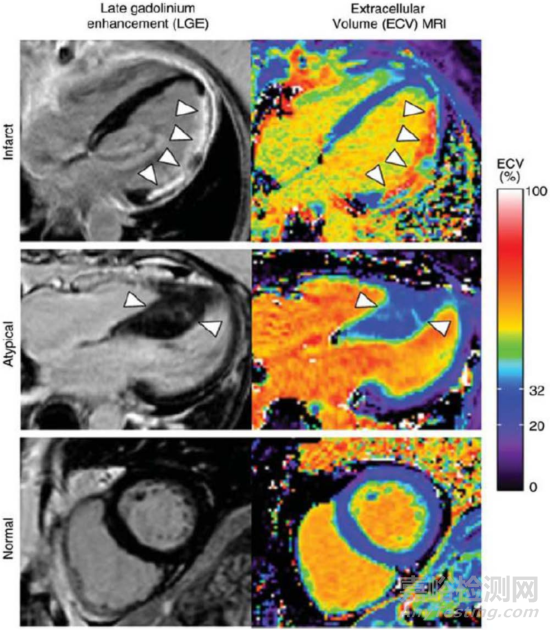

圖12:自由呼吸條件下采集的CMR圖像。圖片引自參考文獻(xiàn)9

心肌組織特性顯像一直是CMR的強(qiáng)項(xiàng),同時(shí)也是準(zhǔn)確量化評估因缺血造成心肌損害的范圍和程度、提示預(yù)后風(fēng)險(xiǎn)的重要技術(shù)手段[10,11]。T1 mapping技術(shù)是無創(chuàng)評估心肌組織特性的新型技術(shù),近年來逐步開始在臨床推廣。通過心臟增強(qiáng)前初始T1值(Native T1)、增強(qiáng)后T1值(Enhanced T1)以及細(xì)胞外容積分?jǐn)?shù)(extracellular volume fraction,ECV)來無創(chuàng)地評估由于纖維化引起的T1值的改變,T1 mapping可定量評估心肌梗死損傷的動態(tài)變化,無創(chuàng)地監(jiān)測組織損傷的演變,也為心肌纖維化的定量評估以及心衰風(fēng)險(xiǎn)預(yù)測提供重要手段。在一定程度上可以成為心肌延遲強(qiáng)化(LGE)在心肌纖維化和肥厚性心肌病(HCM)評估方面的補(bǔ)充和替代,如下圖13所示。T2 mapping技術(shù)是通過測量心肌組織橫向弛豫時(shí)間(T2值)來對心肌水腫進(jìn)行評估的定量技術(shù)。心肌水腫是包括心肌炎和心肌梗死在內(nèi)的多種心肌疾病的重要指征。T2 Mapping技術(shù)正逐步取代傳統(tǒng)的T2加權(quán)成像技術(shù),成為相關(guān)適用癥的優(yōu)選診斷手段。T2* mapping通過對組織T2*弛豫時(shí)間成像,間接反映不同組織器官間的鐵含量情況,實(shí)現(xiàn)對心肌組織鐵代謝的監(jiān)測評估,指導(dǎo)鐵螯合治療。近期多個(gè)臨床研究表明,T2*異常與心肌纖維化、心肌梗死后的微血管損失都有一定的相關(guān)性,因此對于心衰以及急性心肌梗死的評估預(yù)后也有一定的臨床價(jià)值。

圖13:LGE延遲強(qiáng)化顯像與T1 Map ECV顯像的三個(gè)對比示例。圖片引自參考文獻(xiàn)[11]